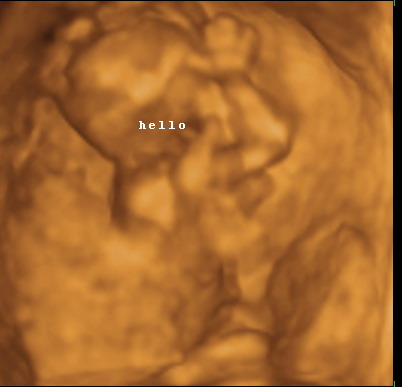

Gratula a kukishoz! Úgy tűnik minden Kisfiúnak ez a szokása! Apa akkor nagyon büszke :lol: :lol: ! Rajta múlt :D ! Kép KUKAC

Kép levitáció Kép Orr+fülfogás

Kép BOX

Kép Lúdtalp nincs :):)lábfej torna Kép Kép Álmos vagyok

Kép guggolás Kép Tipikus pasi-láb között matatás

Kép Nyújtózás

Kép Hello Kép Elég volt, most már alszom